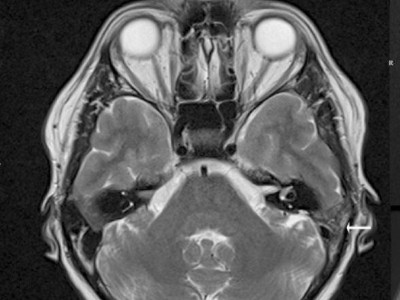

Pulsierende Ohrgeräusche nach Weihnachten – lag es wirklich am Stress?

Eine 48-jährige Patientin leidet seit Weihnachten an pulsierenden, immer lauter werdenden Ohrgeräuschen auf der linken Seite. Eine hohe Stressbelastung kommt zuerst in Frage. Doch schon der erste MRT Befund liefert einen Hinweis auf eine schwerwiegendere, organische Ursache. Hätten Sie das gesehen?

Bildnachweise